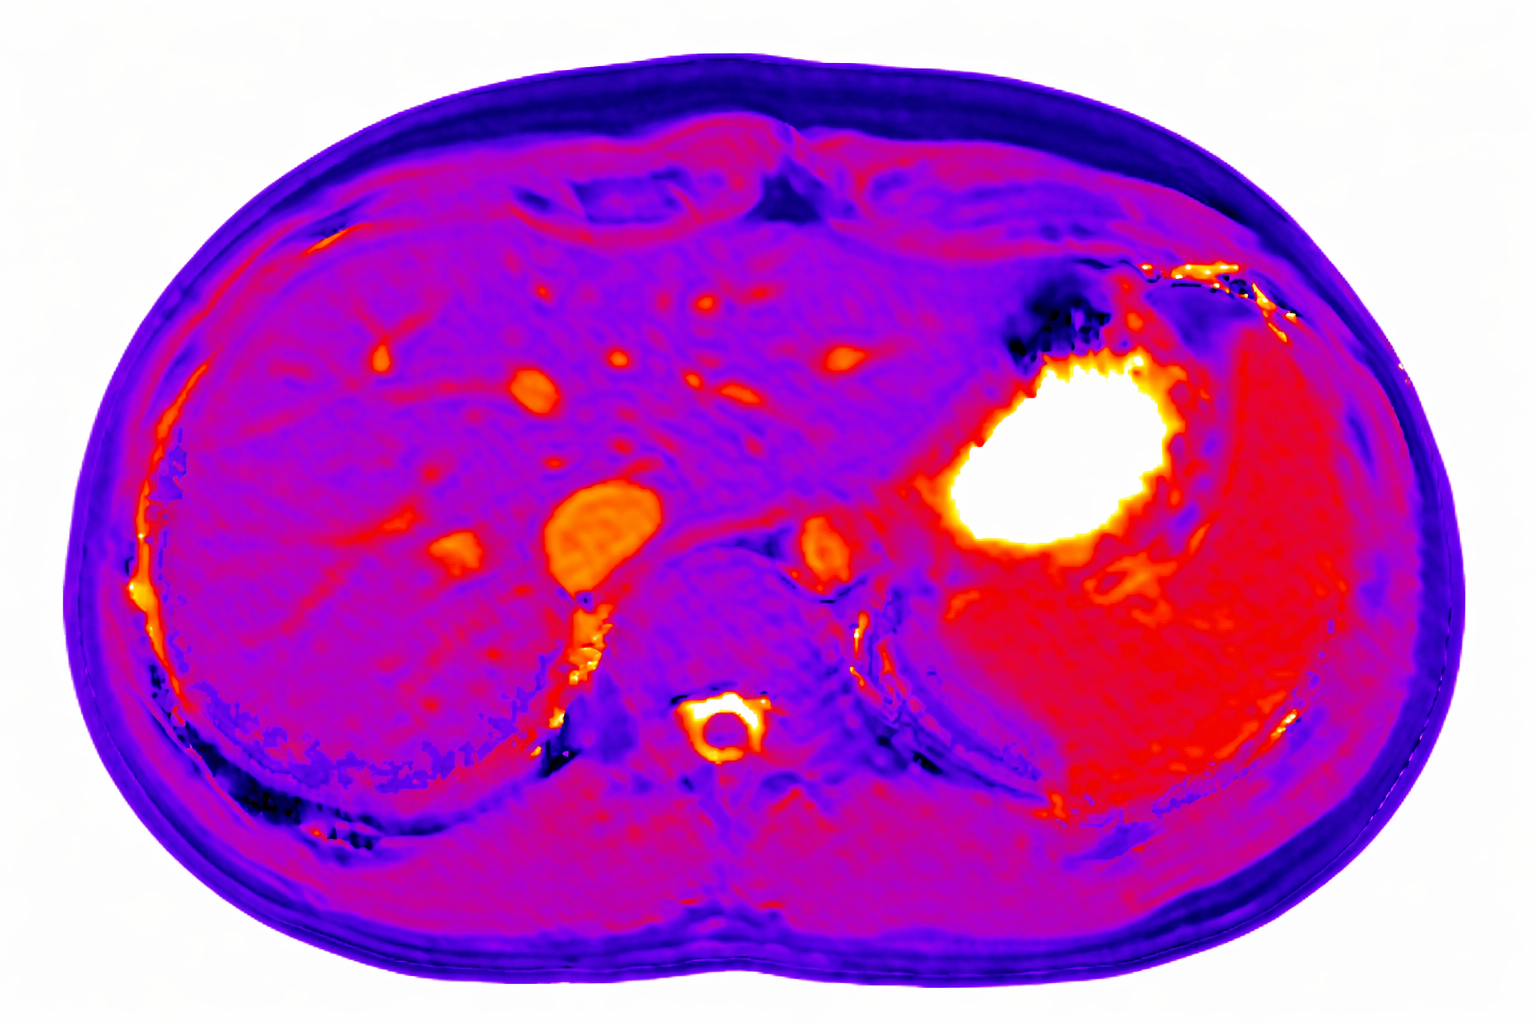

We use dynamic contrast-enhanced MRI (DCE-MRI) of gadoxetate to measure liver transporter function. We use relaxation time measurements to assess tissue status.

Berks M, Little RA, Watson Y, Cheung S, Datta A, O'Connor JPB, Scaramuzza D, Parker GJM, A model selection framework to quantify microvascular liver function in gadoxetate-enhanced MRI: Application to healthy liver, diseased tissue, and hepatocellular carcinoma. Magn Reson Med. 2021 Oct;86(4):1829-1844.